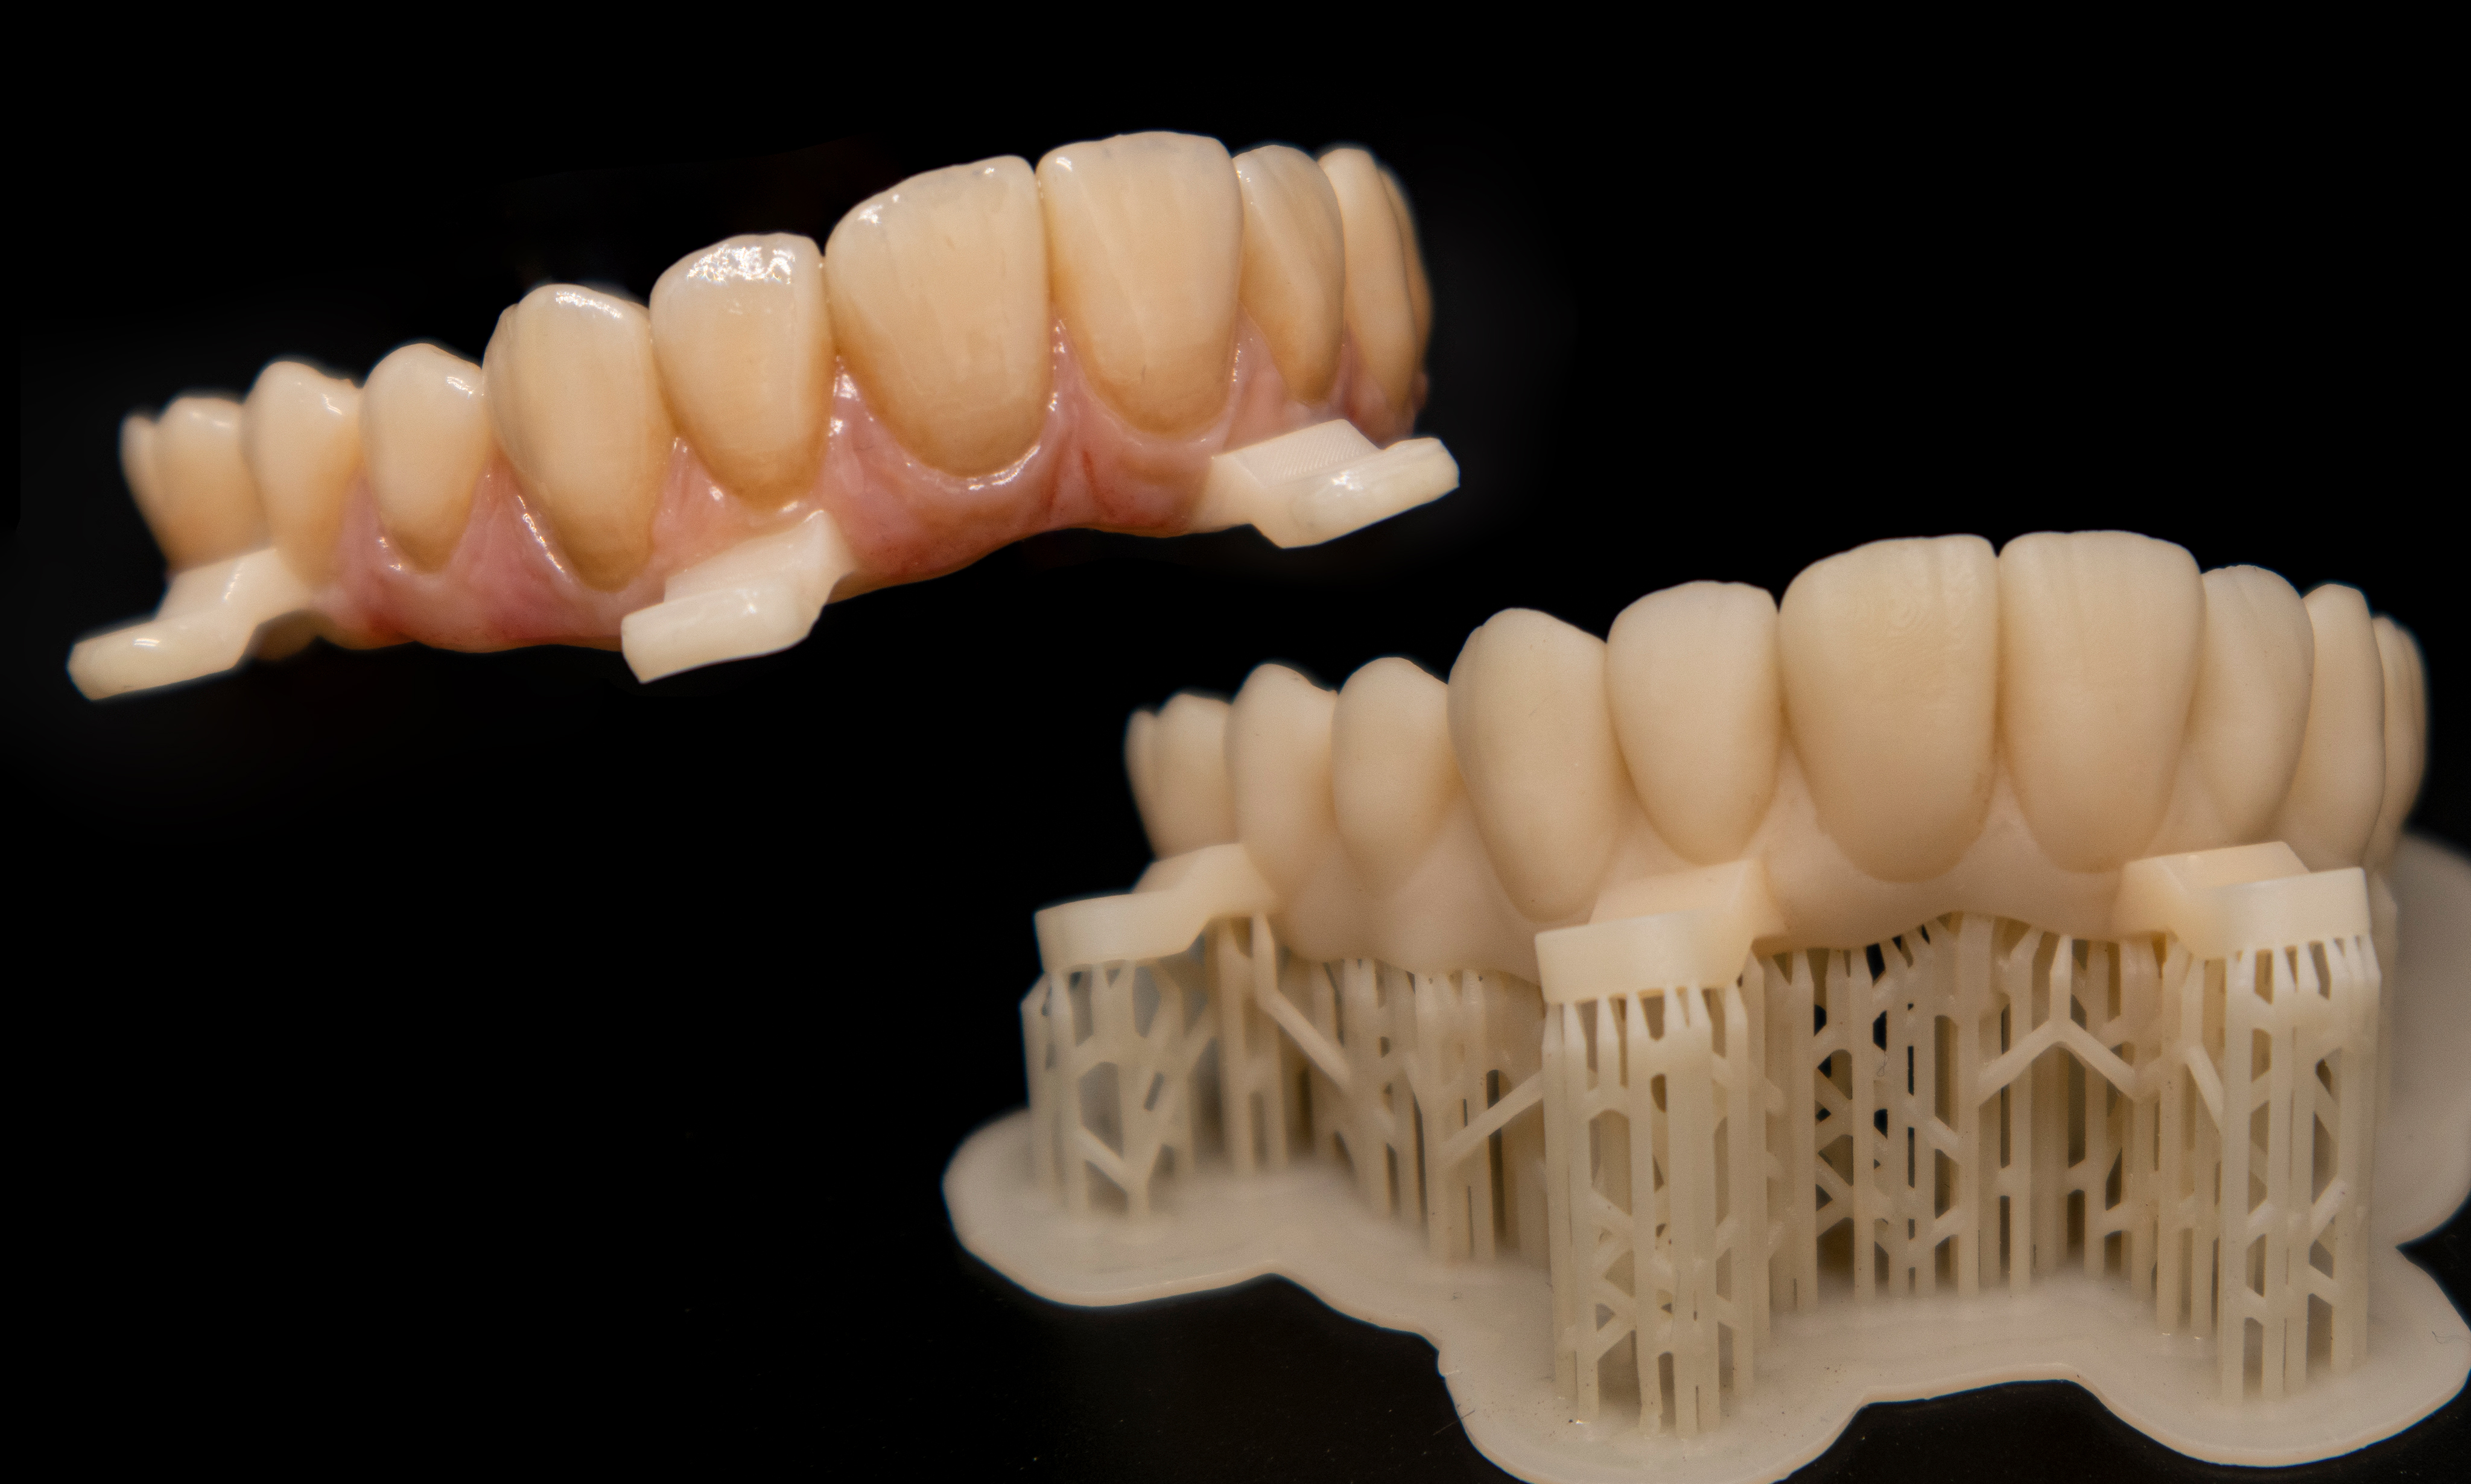

La decisione di utilizzare connessioni IPD MUA Multi Unit Non Engaging (IPD DentalGroup-Abutment Compatibili) ha arricchito ulteriormente il processo, offrendomi la flessibilità necessaria per adattare la protesi in modo che si integrasse perfettamente, non solo con l'aspetto fisico, ma anche con la vita del paziente. Questa scelta, benché tecnica, nasconde un profondo impegno verso il benessere del paziente, un principio che guida ogni nostra azione professionale (Fig. 3). Quando ho osservato la protesi completa per la prima volta, stampata con precisione e poi delicatamente ricoperta in composito, ho sentito un misto di orgoglio e umiltà. Questo non era solo il culmine di un trattamento odontoiatrico, ma la manifestazione fisica della mia passione e dedizione. Ogni dettaglio, dalla selezione dei materiali alla cura nella finitura, era un riflesso del mio viaggio personale nell'odontoiatria digitale (Fig. 4). Condividere questo risultato con il clinico e il paziente è stato un momento che ricorderò per sempre. Vedere la sua espressione trasformarsi, da timida speranza a gioia incontenibile, mi ha ricordato perché ho scelto questa carriera. L'odontoiatria digitale e la stampa 3D non sono solo avanzamenti tecnologici; sono strumenti che, nelle mani giuste, possono trasformare vite. Guardando al futuro, sono elettrizzato dalle infinite possibilità che la stampa 3D porta all'odontoiatria. Ogni giorno nel mio laboratorio è un'opportunità per esplorare, innovare e, soprattutto, fare la differenza nella vita delle persone. La mia storia con l'odontoiatria digitale è appena all'inizio, e sono impaziente di vedere dove questa straordinaria avventura mi porterà.

Il trattamento ha sfruttato tecnologie e materiali d'avanguardia, tra cui RealGuide (3Diemme) per la chirurgia guidata, Exocad per la progettazione dei componenti, e la stampante 3D Dental Makers LB4K 2.0 (DentalMakers Italia), utilizzando materiali specifici per garantire la massima qualità del risultato finale (Fig. 5). Il processo ha iniziato con la scansione delle arcate e l'estrazione del dente residuo, proseguendo con la progettazione e la stampa 3D di una dima chirurgica scomponibile e di una barra di rinforzo personalizzata. La realizzazione di una protesi tipo Toronto Bridge ha completato il trattamento, offrendo al paziente una soluzione ottimale sotto tutti gli aspetti (Fig. 6, Fig. 7, Fig. 8, Fig. 9, Fig. 10, Fig. 11).

La componente protesica MultiUnit e TiBase per MultiUnit sono tutti rigorosamente IPD DentalGroup (IPD AbutmentCompatibili.com). I MUA MultiUnit con la loro ricopertura in TiN coating permette una perfetta stabilità tissutale e un mimetismo cromatico perfetto; il TiBase, anche esso ricoperto in TiN Coating, permette di mimetizzare il componente anche sotto a strutture stampate o con trasparenze e offre una grande sicurezza di adesione grazie alla sua geometria ottimizzata. Un aspetto cruciale di questo trattamento è stato l'uso della chirurgia guidata, che ha permesso un'accurata pianificazione e posizionamento degli impianti con una precisione senza precedenti. Il punto di forza di questa tecnica è l'introduzione delle dime scomponibili, o "stackable", che rappresentano una vera innovazione nel campo. Queste dime permettono di eseguire la chirurgia in fasi multiple, con la possibilità di aggiungere o rimuovere strati per accedere in modo controllato alle diverse fasi del procedimento. Questo sistema, non solo garantisce una maggiore precisione nell'installazione degli impianti, ma riduce anche il tempo chirurgico, minimizzando il disagio per il paziente e accelerando il recupero. L'impiego delle dime stackable dimostra come l'odontoiatria possa beneficiare in modo significativo dell'avanzamento tecnologico, migliorando l'efficienza e l'esito dei trattamenti. La decisione di utilizzare connessioni MUA Multi-Unit Non Engaging (IPD DentalGroup - Abutment Compatibili) è stata guidata dalla necessità di ottimizzare la flessibilità e la funzionalità del trattamento. Queste connessioni offrono una soluzione efficace per gestire la distribuzione delle forze masticatorie, particolarmente vantaggiosa in riabilitazioni complesse come quella realizzata con il Toronto Bridge. La scelta di abutment non engaging ha inoltre favorito una migliore gestione delle discrepanze angolari, facilitando il posizionamento degli impianti e l'adattabilità delle strutture protesiche (Fig .12, Fig. 13). Il trattamento ha portato a risultati eccellenti, migliorando significativamente la qualità di vita del paziente. La protesi tipo Toronto Bridge si è integrata armoniosamente, offrendo un aspetto naturale e duraturo (Fig. 14).